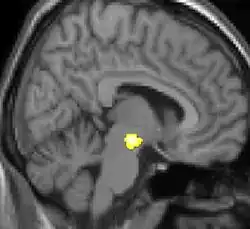

Positron emission tomography (PET) shows brain areas being activated during pain.

Positron emission tomography (PET) scans indicate the brain areas which are activated during attack only, compared to pain free periods. These pictures show brain areas that are active during pain in yellow/orange color (called "pain matrix"). The area in the center (in all three views) is activated only during cluster headaches. The bottom row voxel-based morphometry shows structural brain differences between individuals with and without CH; only a portion of the hypothalamus is different.[36]